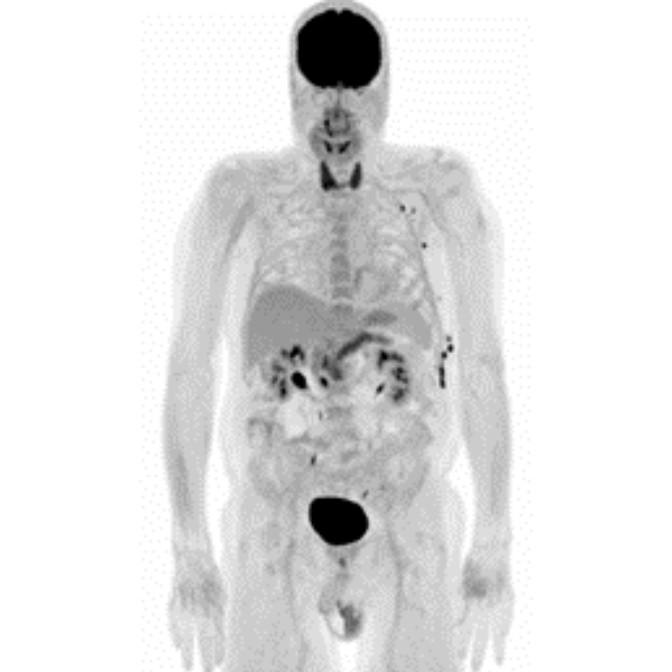

Partial nml and melanoma PET scan

The use of PET/CT in oncology assists physicians in answering clinical questions such as:

The goal of PET/CT imaging in oncology is to enable the physician to distinguish between benign and malignant pathologies, to determine the extent of disease, to detect residual and recurrent tumors, to monitor the effectiveness of treatments, and to guide therapies.